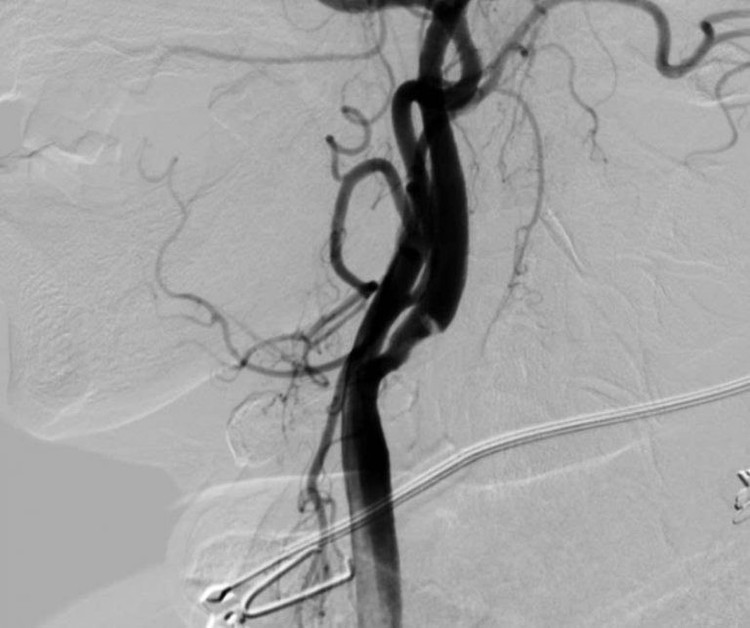

dot-quy-cao-4.jpg

Hình DSA tái thông hoàn toàn động mạch não giữa sau can thiệp của bệnh nhân đột quỵ - Ảnh BVCC

Ngay sau chẩn đoán và giải thích với sự đồng thuận của người nhà, bệnh nhân được chỉ định can thiệp mạch lấy huyết khối bằng dụng cụ.

Ca can thiệp đã diễn ra thành công dưới sự thực hiện của BS Lục Đình Phương, Khoa Sọ não cột sống 2, bác sĩ đã tiến hành tái thông động mạch não giữa và nong bóng đoạn hẹp động mạch cảnh trong bên phải cho bệnh nhân bằng phương pháp gây tê.

Sau can thiệp, các động mạch đã được tái thông, bệnh nhân hoàn toàn tỉnh táo, sức cơ cải thiện rõ rệt và được tiếp tục chuyển lên khoa Nội thần kinh để tiếp tục theo dõi và điều trị theo phác đồ nội khoa.